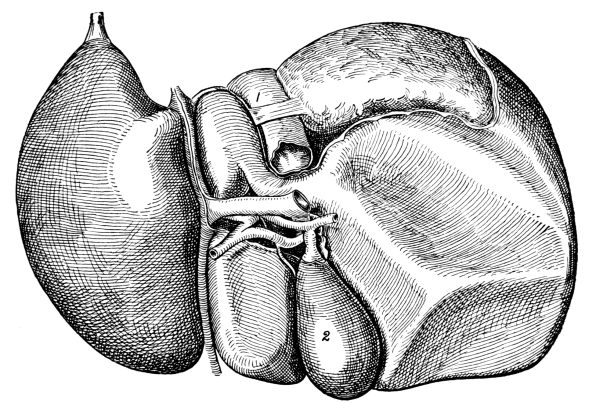

The Abdominal Cavity, 132—Muscles of the Abdomen, 132—The Peritoneum, 134—Abdominal Regions, 134—Salivary Digestion, 136—The Pharynx, 139—The Esophagus, 138—The Stomach, 138—Gastric Digestion, 139—Vomiting, 140—Intestinal Canal, 141—The Small Intestine, 142—Intestinal Digestion, 143—Absorption in Intestine, 144—The Large Intestine, 145—Food and Metabolism, 147—The Liver, 149—The Gall-bladder, 152—The Pancreas, 153—The Spleen, 153—The Suprarenal Capsules, 154—The Kidneys, 155—The Urine, 156—The Ureters, 159—The Bladder and Urethra, 159. |